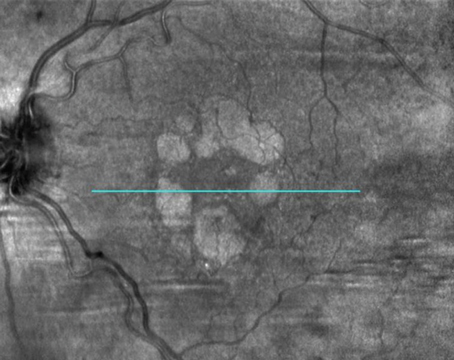

Clinical implications of data from the OAKS and DERBY trials on the future treatment of geographic atrophy.

2023: The year of geographic atrophy